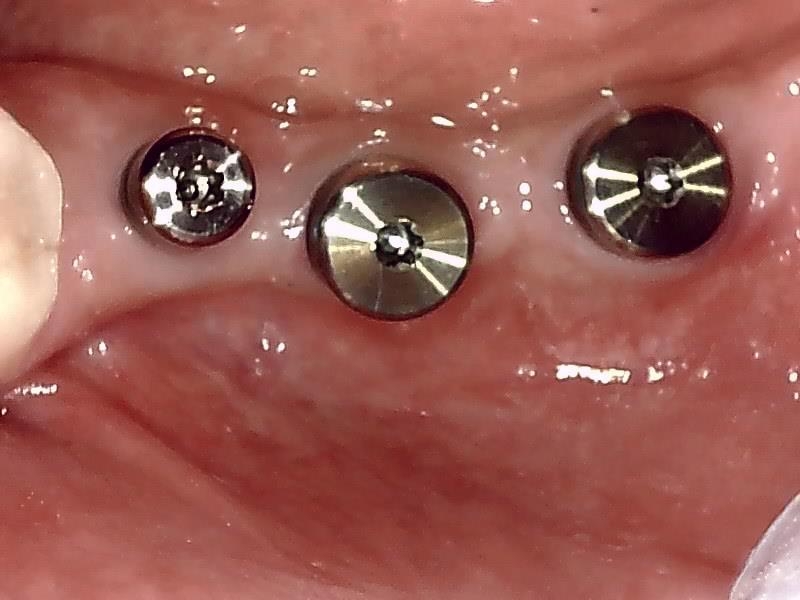

歯肉切開してヒーリングアバットメントの装着している状況です。

ヒーリングアバットメント装着して歯肉を縫合する。

抜糸後、2週間経過した歯肉の状態です。